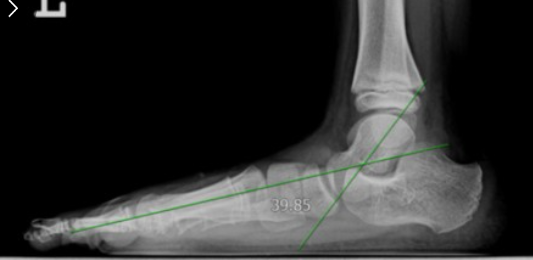

x-ray를 촬영하여 거골과 엄지발가락 중족골 중심 연장선 사이를 측정하여 4도 이상이면 평발입니다

<사진출처: 네이버>

또 다른 방법은 새끼발가락 중족골 및 부분과 종골 밑 부분을 이은 선 사이의 각도가 17도 이하이면 평발입니다.